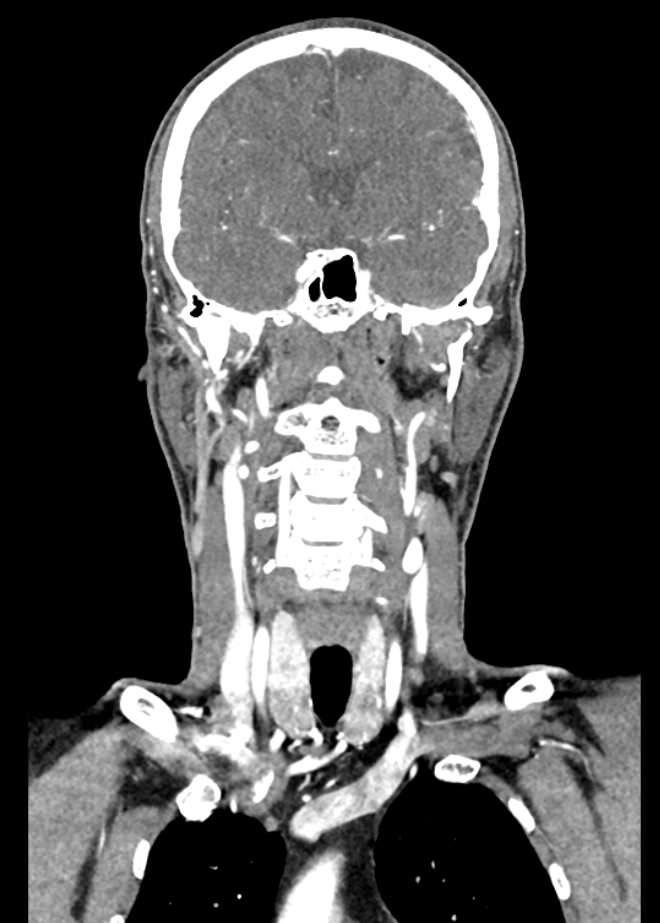

КТ сосудов шеи и головного мозга (КТ-ангиография) позволяет комплексно оценить состояние брахиоцефальных артерий и сосудов головного мозга, включая Виллизиев круг, передние средние и задние мозговые артерии. С помощью КТ-ангиографии можно выявить аномалии развития сосудов (в том числе, аневризмы артерий головного мозга, артериовенозные мальформации), патологические извитости, участки сужения и полной закупорки просвета сосуда. КТ-ангиография покажет утолщение стенки артерии, точную локализацию атеросклеротической бляшки, стенозы и окклюзии просвета сосудов, степень функционирования Виллизиева круга, что бывает особенно важно при планировании оперативного вмешательства и для оценки эффективности хирургического лечения.

В нашей клинике КТ сосудов шеи и головного мозга выполняется на современных мультиспиральных компьютерных томографах экспертного уровня TOSHIBA AQUILION. Для визуализации сосудистой системы в обязательном порядке проводится контрастное усиление. Для этого в вену пациенту вводится йодсодержащий контрастный препарат, который хорошо поглощает рентгеновские лучи и обеспечивает яркую видимость сосудистой сети на фоне окружающих тканей.

Высокотехнологичное оборудование последнего поколения обеспечивает высокую точность и контрастность изображений, благодаря чему получаются снимки и трехмерные модели сосудистой системы высокого качества. Увеличенное количество детекторов позволяет производить одномоментно множество послойных снимков, что значительно сокращает время исследования и минимизирует уровень лучевой нагрузки на организм пациента.